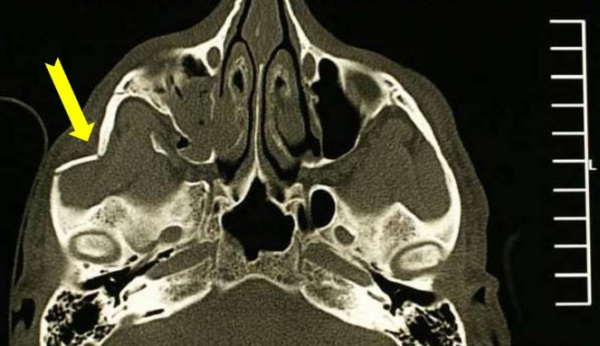

Сочетанные переломы скуловой кости со скуловой дугой, а также глазничного края с дном глазницы (латеральный перелом средней части лицевого скелета) наблюдаются часто. Возможны также изолированные разрывные переломы дна глазницы и изолированный перелом скуловой дуги.

Переломы скуловой кости и глазницы могут быть также частью тяжелых переломов костей средней части лица или лобно-базальных переломов. Почти всегда повреждается верхнечелюстная пазуха. Механизм переломов состоит в тупом ударе большой силы по боковой части лица, например ударе кулаком или ударе, полученном в дорожной аварии или при падении с лестницы. Переломы этой локализации почти всегда бывают вдавленными.

а) Признаки перелома глазницы и скуловой кости. Включает гематому глазницы, отек век, асимметрию средней трети лица с западением контура щеки на стороне перелома, смещение вниз, а также энофтальм на стороне перелома, образование ступеньки на нижней или латеральной стенке глазницы, изредка - верхнем крае глазницы, а в части случаев тризм.

Мягкие ткани в скуловой области быстро отекают, но контуры скуловой кости бывают уплощены. Возможна потеря чувствительности в зоне иннервации подглазничного нерва. При взрывном переломе движение глазного яблока частично ограничено, появляется диплопия, связанная с ущемлением нижней прямой или нижней косой мышцы.